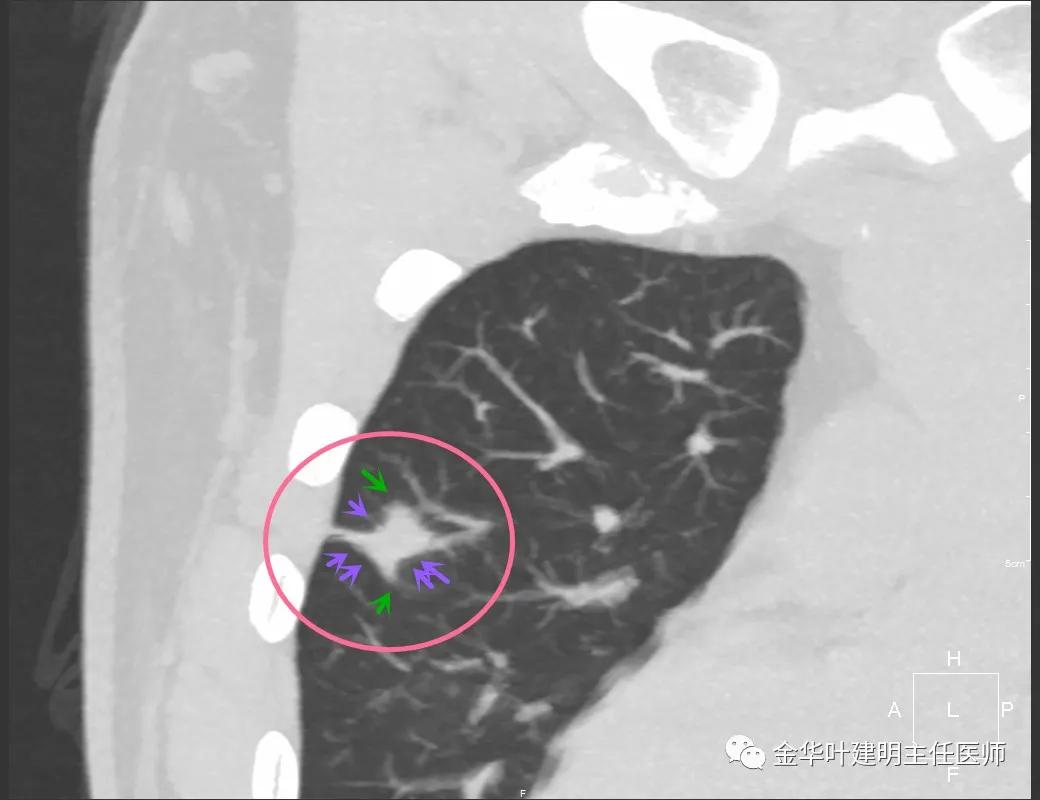

实性部分我看是有所缩小改善的,边上磨玻璃样的晕征更加明显了点

上图示病灶边缘向内凹陷,同时仍伴晕征

上图红色箭头示仍有血管进入,但蓝色箭头示边缘内凹,绿色示仍有晕征

上图红色箭头示血管进入病灶